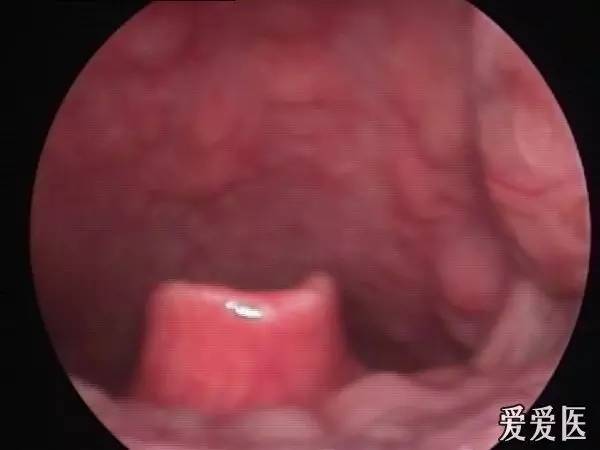

正常会厌

喉镜下会厌

口咽部检查多无明显改变,易被忽略,但是剧烈咽痛无法解释。只要采用间接喉镜检查,即可发现会厌明显充血、肿胀、严重时呈球形。如会厌脓肿形成,红肿黏膜表面可见黄白色脓点。由于肿胀会厌遮盖,声门是看不到的。